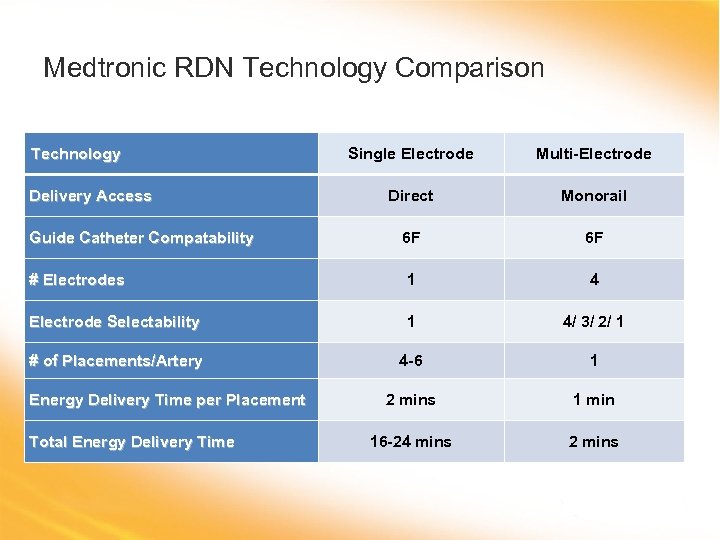

Medtronic RDN Technology Comparison Technology Single Electrode Multi-Electrode Direct Monorail 6 F 6 F # Electrodes 1 4 Electrode Selectability 1 4/ 3/ 2/ 1 # of Placements/Artery 4 -6 1 2 mins 1 min 16 -24 mins 2 mins Delivery Access Guide Catheter Compatability Energy Delivery Time per Placement Total Energy Delivery Time

Medtronic RDN Technology Comparison Technology Single Electrode Multi-Electrode Direct Monorail 6 F 6 F # Electrodes 1 4 Electrode Selectability 1 4/ 3/ 2/ 1 # of Placements/Artery 4 -6 1 2 mins 1 min 16 -24 mins 2 mins Delivery Access Guide Catheter Compatability Energy Delivery Time per Placement Total Energy Delivery Time